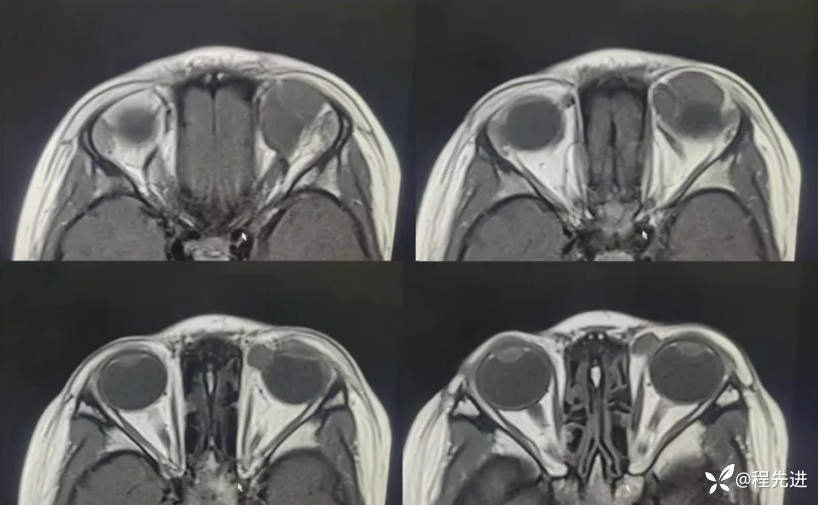

MRI平扫+增强:

T2:

T1: